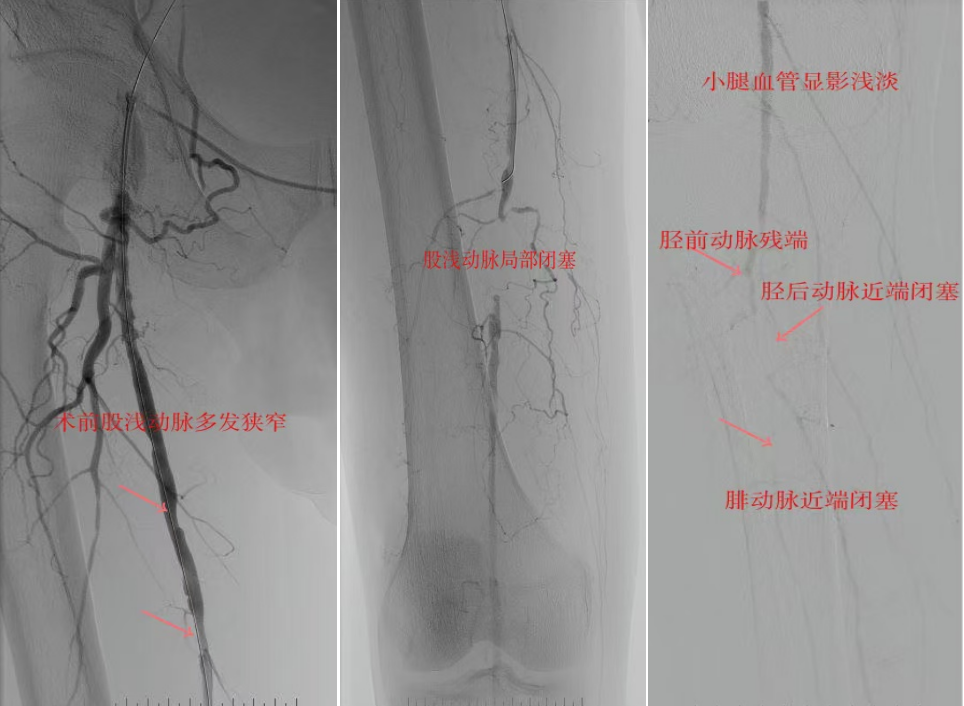

78岁男性患者,糖尿病合并高血压、脑梗塞,右足持续疼痛伴冰凉发绀3个月。入院CTA显示其右侧股浅动脉全程闭塞,膝下三支动脉均闭塞。医疗团队在局部麻醉下,再次巧妙应用“逆向开通技术”,经胫后动脉——足底弓逆向开通足背动脉及胫前动脉。术后患者右足皮温即刻回升,疼痛消失。术后结合中药外治(换药、熏洗、去腐生肌膏外敷)加速创面愈合,患者已顺利出院。

影像检查:CTA显示右侧股浅动脉全程闭塞,膝下三支动脉(胫前、胫后、腓动脉)完全闭塞。

两例患者共同凸显三大高难度治疗挑战:1.患者高龄且基础病复杂;2.血管全程多节段闭塞、钙化程度严重;3.常规顺向开通路径已被完全阻断。团队果断采用远端逆行穿刺技术,在纤细的足踝部血管建立治疗通道,实现“逆向破冰”。